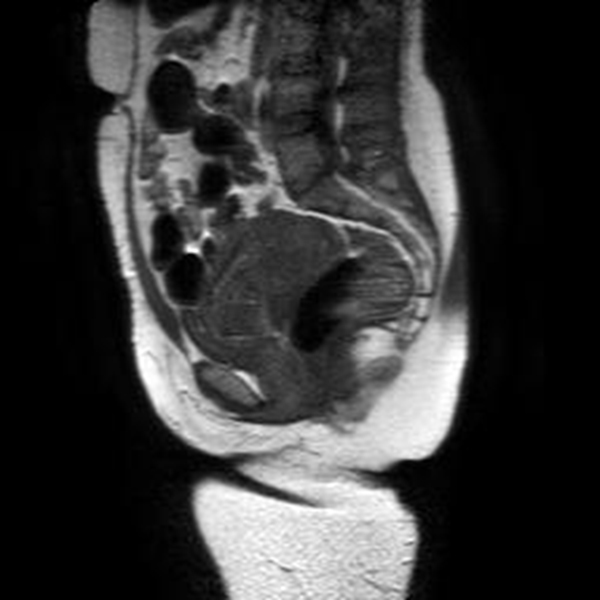

Se realizó una RNM (Philips 1.5 Tesla) que permitió confirmar el diagnóstico de EEC (figuras 5 a 8).

El propósito de la RMN es aportar información adicional para mujeres que necesiten un diagnóstico preciso, caracterización del tejido y ubicación espacial. Algunas indicaciones de la resonancia en el EE son las complicaciones asociadas, hallazgos ecográficos no concluyentes o complicaciones del EE, como las localizaciones abdominal, intersticial, miometrial o cervical (26).

La localización cervical de un EE por debajo del orificio cervical interno puede confundirse con un aborto espontáneo en curso, con enfermedad trofoblástica, con un pólipo endometrial que protruye por el canal cervical o con una placenta de implantación baja (27).

Jung y cols. (28) encontraron como hallazgos en RMN de EEC una masa mal definida con señales muy heterogéneas en T2, hiperintensidades internas e irregulares en T1, con un anillo circunferencial o parcial de baja intensidad de señal, con realce periférico irregular del componente sólido papilar, acompañado de vacíos de señal de morfología tubular. Esto va en concordancia con lo referido por Tamai y cols. (27), que describen típicamente el EEC como una masa hemorrágica, heterogénea y con realce intenso de los componentes papilares del tejido.

Una secuencia útil en la identificación del hematoma reciente es el T2*, que podría remplazar el uso del gadolinio en esta indicación particular. La sensibilidad del 95 % y la especificidad del 100 % de esta secuencia mejora significativamente el desempeño de la resonancia en el diagnóstico de EE (29).

El uso de gadolinio intravenoso incrementa la especificidad en el diagnóstico de embarazo tubárico, lo que permite diferenciar el realce normal de la trompa de un hematoma reciente. En este caso, este principio nos ayudó a delimitar la afectación decidual y a descartar la presencia de un hematoma asociado (30). La resonancia con gadolinio también se ha utilizado en el seguimiento del tratamiento conservador del EEC (31).